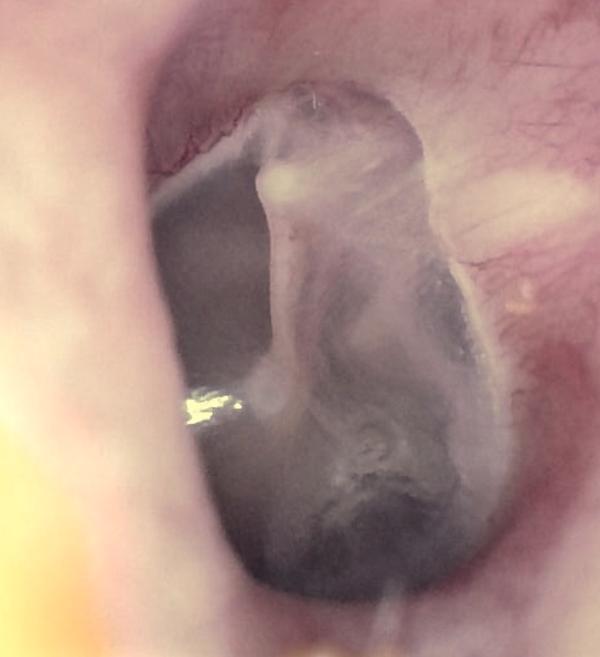

Pars Flaccida Retraction

Pars Tensa Retraction